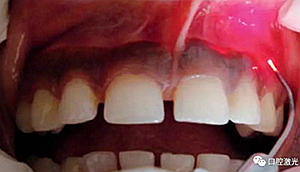

患者22歲,女性,主訴牙齦發(fā)黑??谇粰z查顯示牙齦部位呈黑色,但軟組織健康,沒有表皮粗糙或水腫現(xiàn)象。計(jì)劃使用半導(dǎo)體激光進(jìn)行治療。手術(shù)前患者無需表麻或局麻。采用光纖接觸方式,激光功率設(shè)定為1.5W至2W,連續(xù)模式。氣化黑色牙齦區(qū)域上皮組織。不斷重復(fù)該過程,直至足夠深度的牙齦軟組織表皮被去除干凈?;颊咝g(shù)后需采用漱口水進(jìn)行口腔護(hù)理。

術(shù)后一周